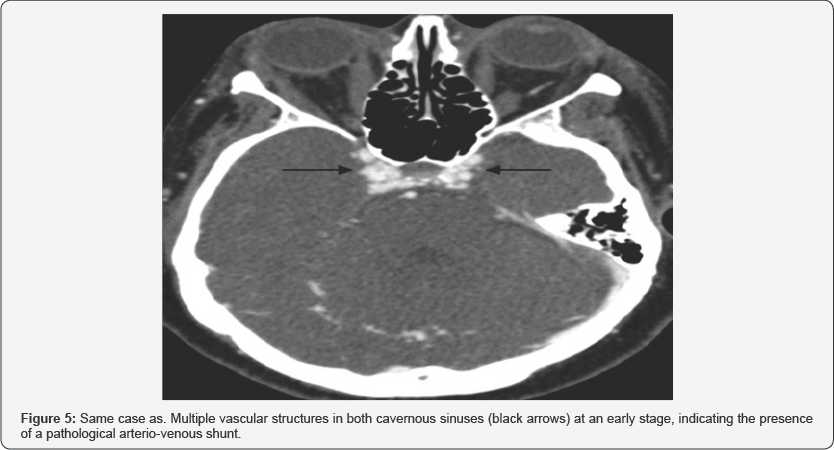

CT is usually the initial test in the CCF study. The study by helical acquisition and 3D post-processing has contributed significantly to the diagnosis of this entity. The findings that we can observe in these studies and that allow us to establish the diagnosis of CCF are fundamentally an enlarged cavernous sinus that enhances asymmetric and early with an early filling of the plexuses, venous sinuses and ophthalmic veins (Figure 5). It also allows the evaluation of orbital signs such as proptosis and thickening of the extraocular musculature (Figure 6), and in cases of direct CCF, of traumatic etiology, it allows to identify the fracture traces in the skull base [5].